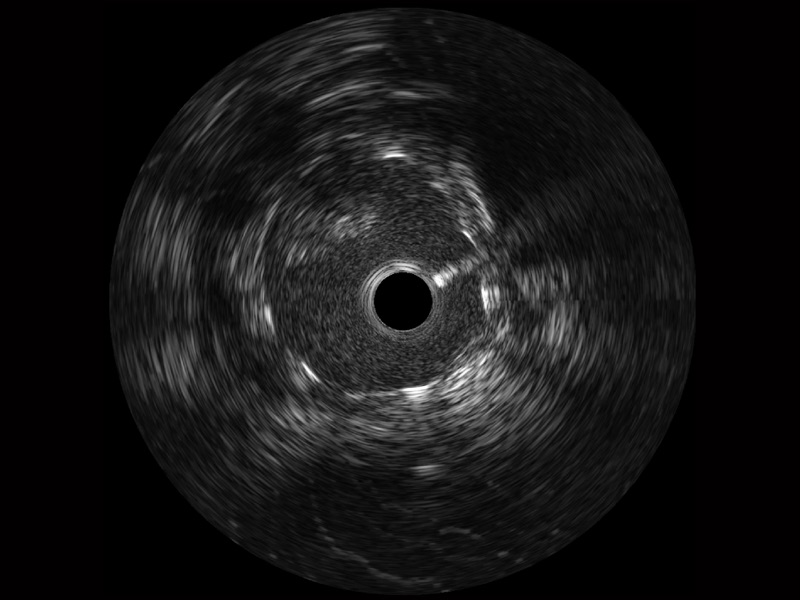

• 百老汇电子游戏官网宽频IVUS图像

• 传统IVUS图像

对比传统IVUS导管成像,百老汇电子游戏官网宽频IVUS图像的近场支架梁显影更细腻,远场中膜外血管仍清晰可辨,兼顾远中近,兼顾分辨力与穿透深度